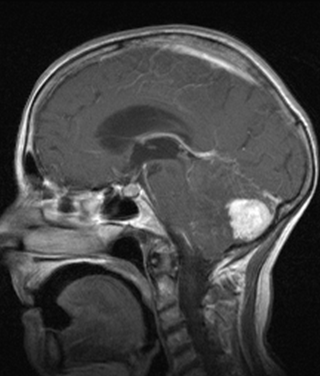

Craniopharyngioma:

Originates from the remains of the epithelial cells of Rathke’s pouch.

CT can reliably differentiate its three components (calcification can already appear on conventional X-ray images, but it is certainly detectable with CT). MRI can also differentiate its 2 or 3 components based on their characteristic signals.

Arnold – Chiari malformation

Type I. the cerebellar tonsil appears pointy and extends below the level of the foramen magnum, but it does not exceed 5 mm.

In Type II. the caudal part of the cerebellum also extends below the foramen magnum while the medulla oblongata and IV. ventricle sink to the widened segment of the spinal canal. It is accompanied by neural tube closing disorders.

Type III is the combination of type II. with occipital cephalocele.

Radiologically they are the best depicted in sagittal (+ coronal) imaging planes.